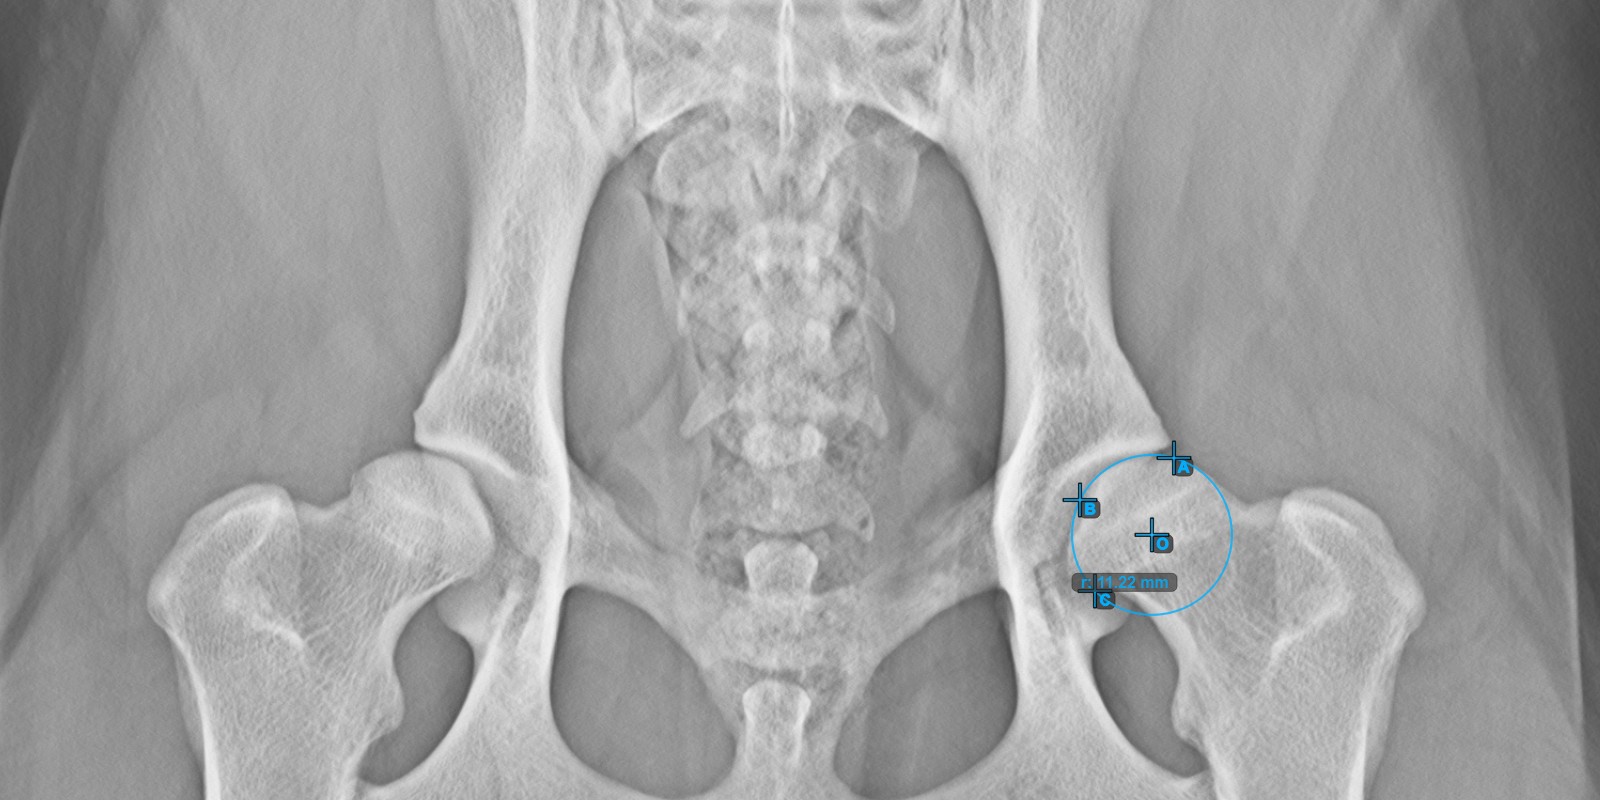

Berechnen Sie den linken Norberg-Winkel, indem Sie eine Linie an der effektiven Kante des linken Acetabulumknochens markieren.

Setzen Sie einen Punkt in der Nähe des linken Caput Femoris und ziehen Sie ihn entlang der effektiven Kante des linken Acetabulumknochens, um die Schenkelseite des linken Norberg-Winkels zu bilden.

Die gezeichnete Linie muss eine Tangente an der effektiven Kante des linken Acetabulumknochens sein. Der Wert und der Bogen des Winkels werden automatisch berechnet.

Das Bild unten zeigt die typische Platzierung der Linie und die berechnete Norberg-Winkel-Messung.

../../_images/image288.jpg